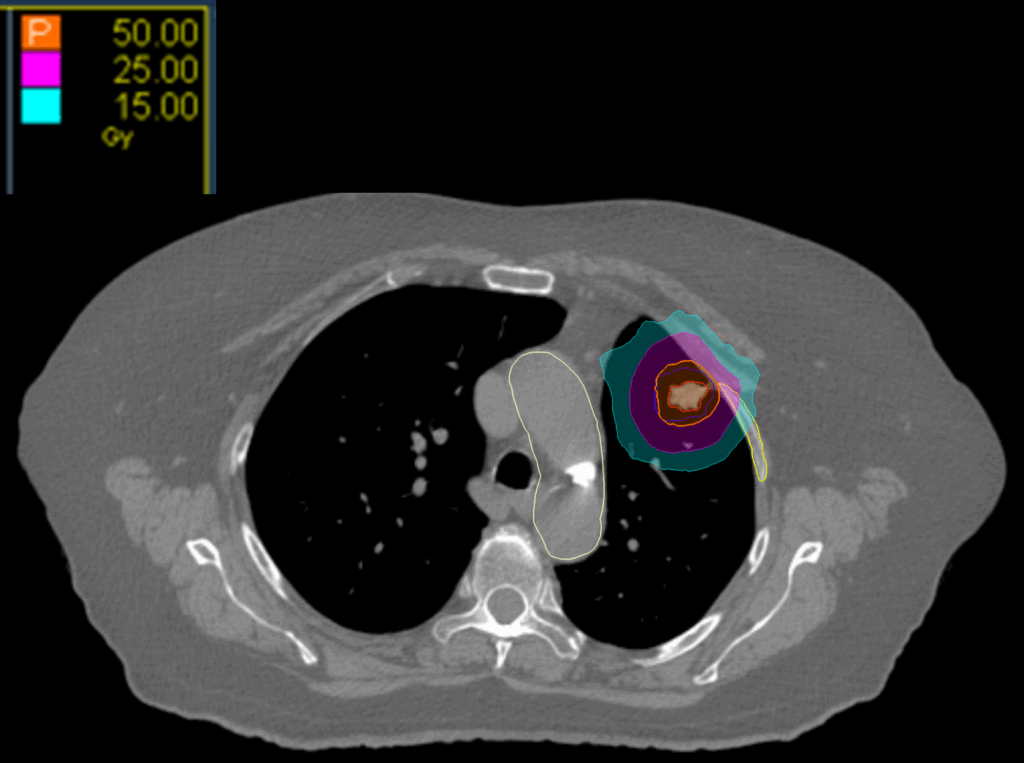

Treatment Plan Images

Fractionation

50 Gy in 5 fractions

Dose Distributions

- Prescription to the

71.7% isodose line - Max. dose 69.7 Gy

New Conformality Index (nCI)

nCi = 1.51

Gradient Index (GI)

GI = 4.51